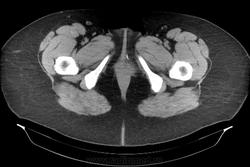

Инородное тело. Хирургическая игла.

Хирургическая игла, которую оставили гинекологи.

Да, гинекологи сами почуяли неладное и отправили пациентку на исследование. Операция была по поводу кисты левой бартолиневой железы. Со слов пациентки, ей до этого делали УЗИ, но ничего не обнаружили. Расположена она в толще большой половой губы, в преддверии влагалища.